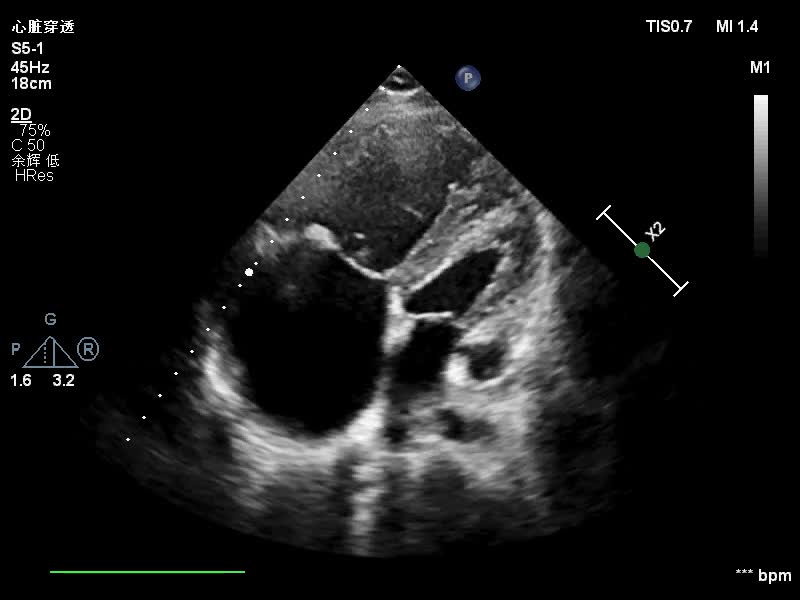

推荐男性,45岁,幼年时查出心脏问题,因经济原因未及时进行治疗,今因心悸前来就诊。经过询问得知,患者平时喜蹲踞,不喜欢坐站,但指端末梢未见明显紫绀,超声图像如下:

超声报告如下:

二维:(胸骨旁左室长轴切面、心底短轴切面)

①、主动脉前壁与室间隔连续性中断(室缺常为 嵴下型);

②、主动脉增宽,前壁前移,骑跨于室间隔之上;

③、肺动脉口狭窄,大多数为漏斗部狭窄;

④、右心室肥厚。